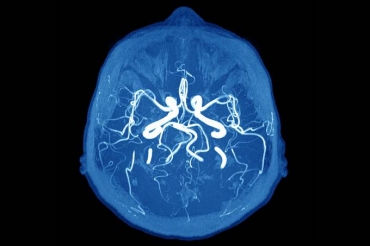

Os especialistas indicam alguns testes que podem ser feitos para ajudar a identificar o derrame: pedir à pessoa que sorria com força (observar simetria e possíveis desvios da face); pedir que levante os braços; que responda com frases simples a comandos de baixa complexidade. Caso se confirme a suspeita clínica de AVC, o paciente dever ser imediatamente submetido a uma tomografia computadorizada (TC) ou ressonância magnética (RM), que mostrarão se o AVC foi isquêmico ou hemorrágico. Esses exames são fundamentais para o diagnóstico do AVC na fase aguda e determinação do prognóstico e tratamento mais adequado.

O aneurisma cerebral é um problema genético e hereditário, caracterizado por uma fraqueza da parede do vaso sanguíneo que ocasiona uma dilatação anormal. Segundo Peixoto, no Brasil existem cerca de 2 milhões de casos por ano conhecidos de aneurisma cerebral. “O principal sintoma de um aneurisma é uma dor de cabeça frequente e que não cessa após a administração de analgésicos.” Mas, muitas vezes, o paciente não apresenta nenhum sintoma e o problema não é identificado. Daí a importância de filhos cujos pais tiveram um aneurisma detectado realizarem, a partir da puberdade, uma angiorressonância para verificar a existência – ou não – do problema.

As opções disponíveis de tratamento seriam a cirurgia por clip ou a embolização por micromolas. Por outro lado, se não houver necessidade de intervenção, é importante que o paciente faça um acompanhamento anual da evolução do quadro por meio de uma angiorressonância.